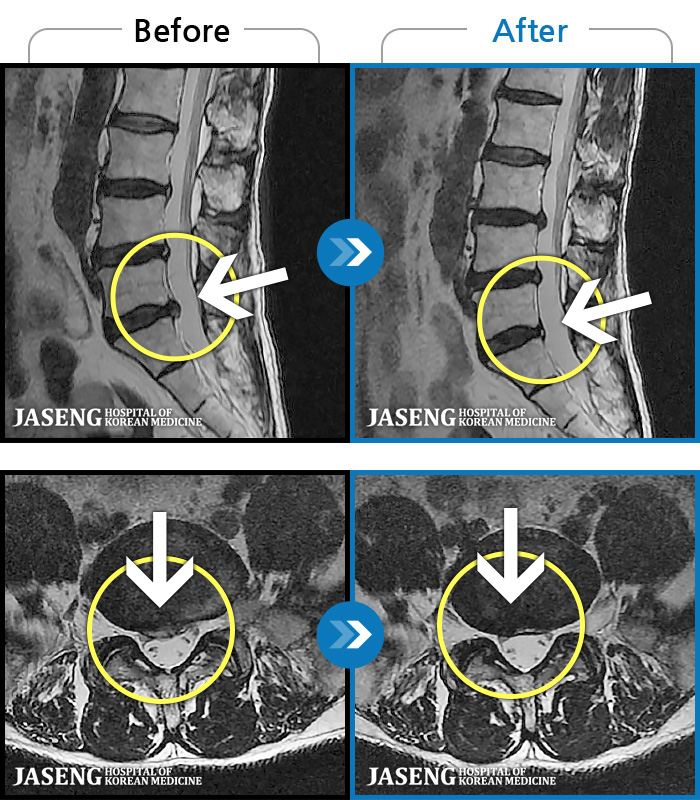

MRI ũ ʸ Ȯϼ.